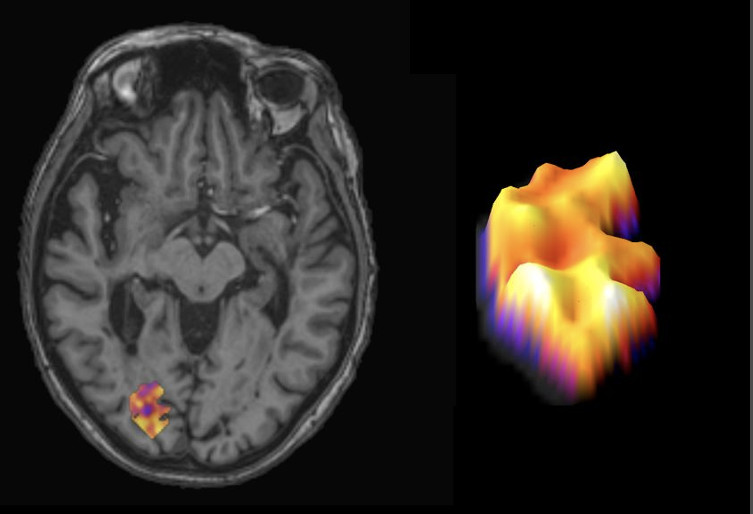

Turun yliopiston tutkijat ovat löytäneet uuden ennustetekijän, joka kertoo MS-taudin etenemisnopeudesta. Uuden tiedon mukaan aivojen tulehduspesäkkeiden reunojen paksuus on yhteydessä taudin vaikeusasteeseen ja etenemisvauhtiin. Löydös syntyi professori, InFLAMES-ryhmänjohtaja Laura Airaksen johtamassa tutkimusryhmässä. Tutkimustulokset on julkaistu 29.4. Nature Medicine -lehdessä.

MS-taudin tautipesäkkeet, leesiot, ovat syvällä aivoissa, mutta ne pystytään paikallistamaan ja näkemään PET-kuvauksella. Airaksen ryhmä yhdisti kuvantamistiedot näytteisiin, jotka on otettu MS-potilaiden aivoista heidän kuolemansa jälkeen. Kudosnäytteet tulivat Hollannista ja kuvantamistietoa kerättiin 114 suomalaiselta MS-potilaalta. Tuloksista nähtiin, että mitä leveämpi reunus tautipesäkkeissä on, sitä nopeammin etenevästä taudista on kyse.

– Kun mikrogliat muodostavat tällaisen leveän ja paksun reunuksen, niiden haitallinen toiminta työntyy syvemmälle terveeseen aivokudokseen ja vaurioittaa sitä, Airas selittää.

Hän valottaa asiaa tennispallovertauksella: jos MS- tautipesäke olisi kuin tennispallo, rauhallisessa mikrogliatoiminnassa pallon pintaa peittäisi matala nukka. Erittäin aktiivinen mikrogliatoiminta taas vastaisi sitä, että tennispallon pintaa peittäisi pitkä karva.